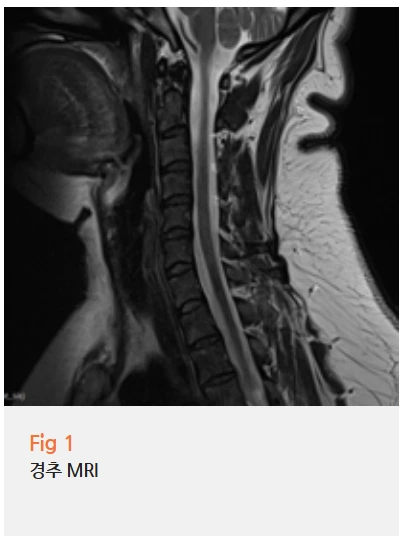

환자분께 당일 MRI 검사를 권유드렸고, 결과에서 경추 부위의 경미한 추간판 변성이 확인됐어요.

흔히 목 디스크라고 하면 목이 아프거나 팔이 저린 증상을 먼저 떠올리시죠.

물론 그런 경우가 가장 흔하긴 해요.

그런데 경추 신경이 자극을 받았을 때 통증이 나타나는 위치는 사람마다, 신경 레벨마다 다를 수 있어요.

경추 5번, 6번, 7번 신경이 각각 다른 경로로 팔과 어깨, 겨드랑이 쪽으로 뻗어 있기 때문에,

어느 레벨에서 문제가 생겼느냐에 따라 통증의 위치도 달라져요.

이 환자분의 경우, 겨드랑이 부위에 방사통이 나타난 게 그 이유였어요.

목에서 시작된 문제가 겨드랑이 아래 통증으로 표현된 것이었죠.